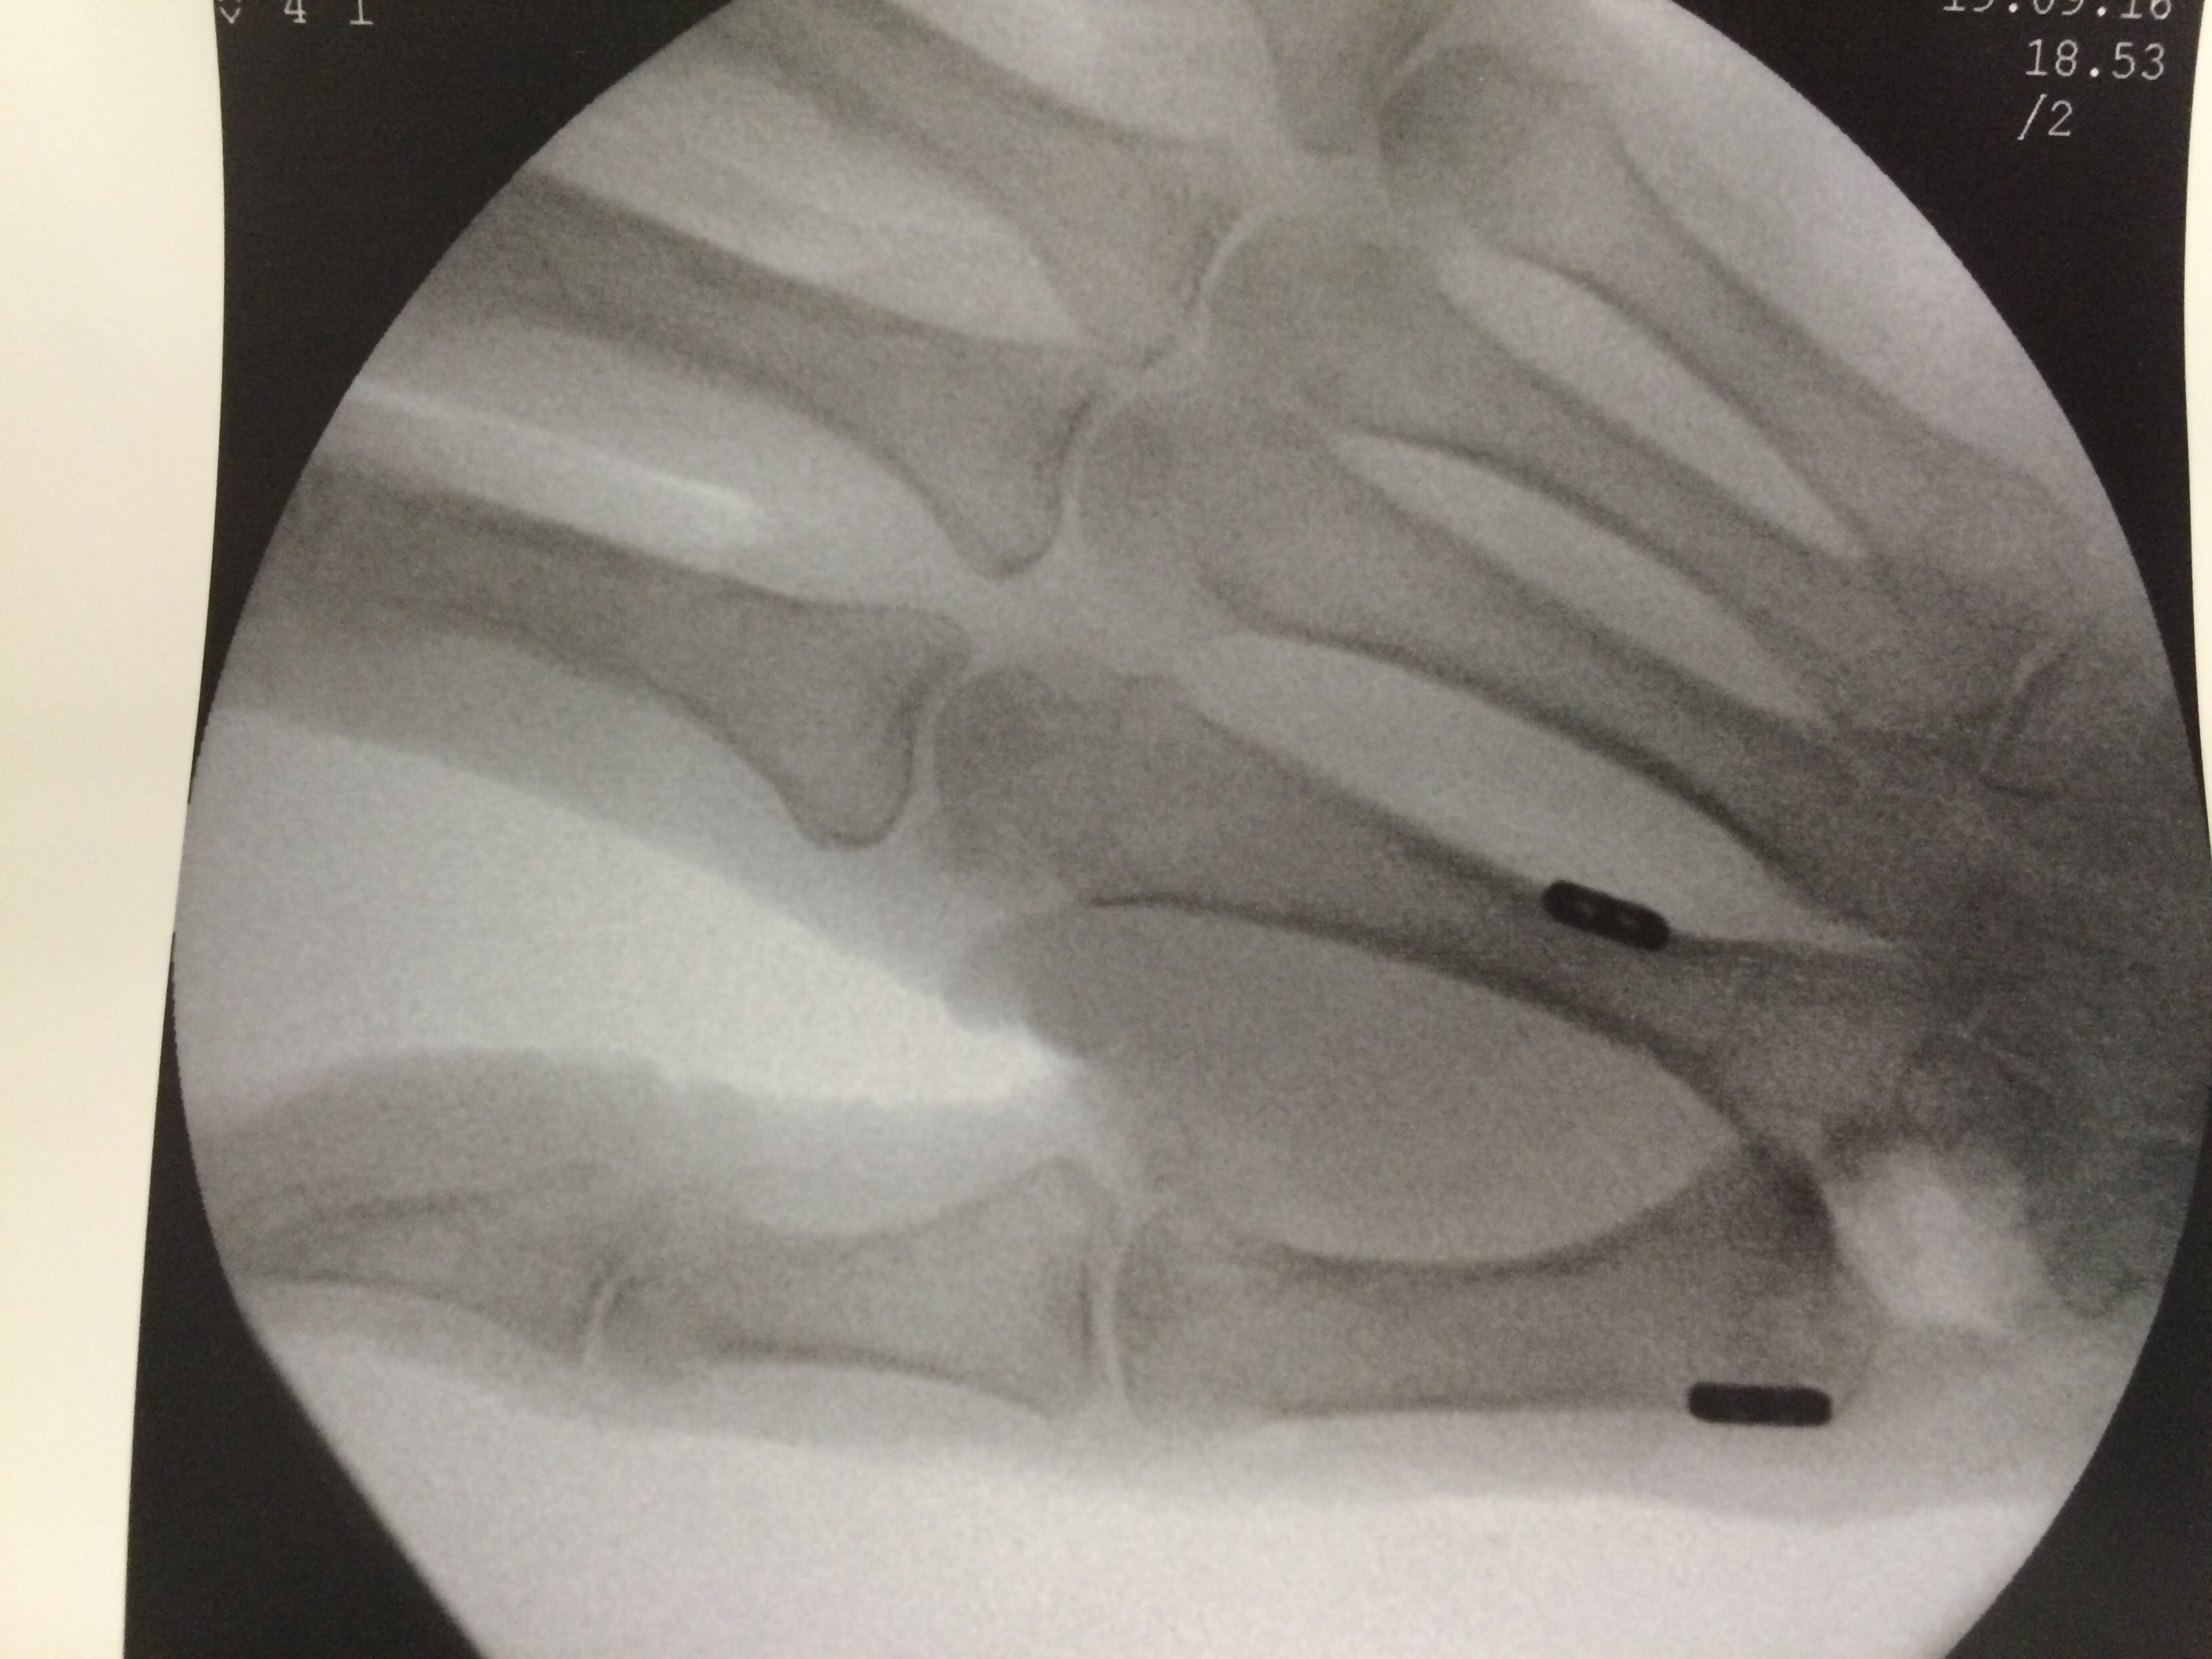

Mallet Finger is easily diagnosed due to its unique presentation. X-rays will be ordered to assess for the presence and extent of bone fracture. This aids in determining the appropriate treatment plan.

TREATMENT

Most cases of Mallet Finger can be treated without surgery, as long as there are no large bone fractures. A special finger splint may be applied to hold the digit in proper alignment while the tendon heals. The splint is worn continuously for 6 weeks, then at night for an additional 6 weeks. Surgical repair may be considered when mallet finger injuries have large bone fragments or joint mal-alignment. In these cases wires or even small screws are used to secure the bone fragment and realign the joint or to do a temporary fusion of the distal interphalangeal joint.